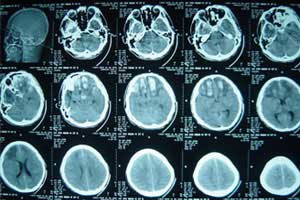

颅骨骨折较常见,往往是由于钝性暴力或穿透性损伤造成,大多无需特殊处理,故骨折本身并不重要。

但颅骨骨折的发生与暴力作用的方向、大小、减速距离等密切相关,由于颅骨骨折常并发脑、脑膜、颅内血管和神经的损伤,若处理不及时,可引起颅内血肿、脑脊液漏、颅内感染等并发症,影响预后。

如果打击的强度大、面积小、多以颅骨的局部变形为主,常致凹陷性骨折,伴发的脑损伤也较局限;若着力的面积大而强度较小时则易引起颅骨的整体变形,而发生多发线形骨折或粉碎性骨折,伴发的脑损伤亦较广泛。